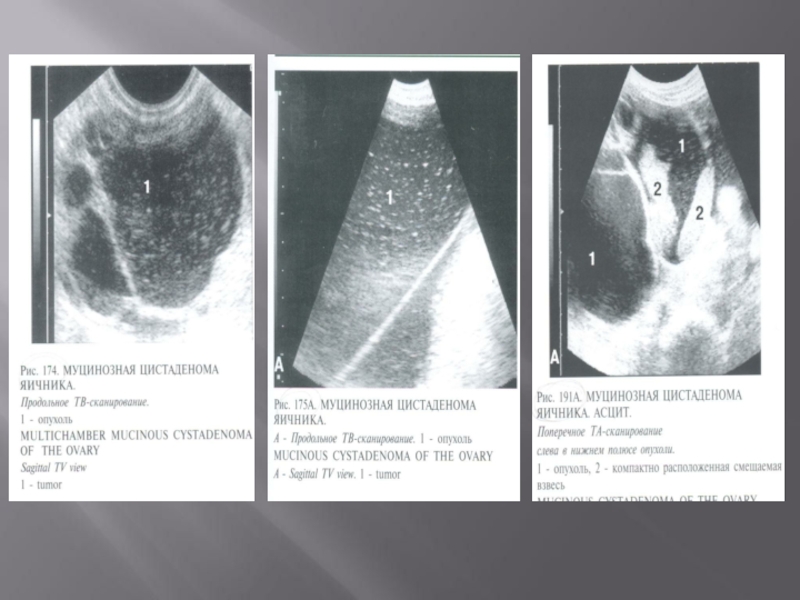

Слайд 36 Фолликулярные - 83%

 Кисты желтого

тела - 5%

 Эндометриоидные - 10%

 Текалютеиновые

- 2%

 Фолликулярные     - 83% Кисты желтого тела  - 5% Эндометриоидные